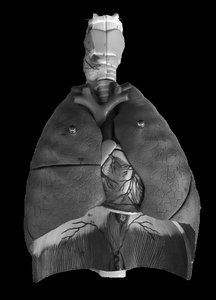

Lung Lobes and Fissures

Lobes of the Lungs

Right Lung: Three lobes – upper, middle, and lower.

Left Lung: Two lobes – upper and lower; contains the cardiac notch for the heart.

Fissures: Oblique and horizontal fissures separate the lobes.

Hilum: The entry/exit site for bronchi, blood vessels, and nerves.